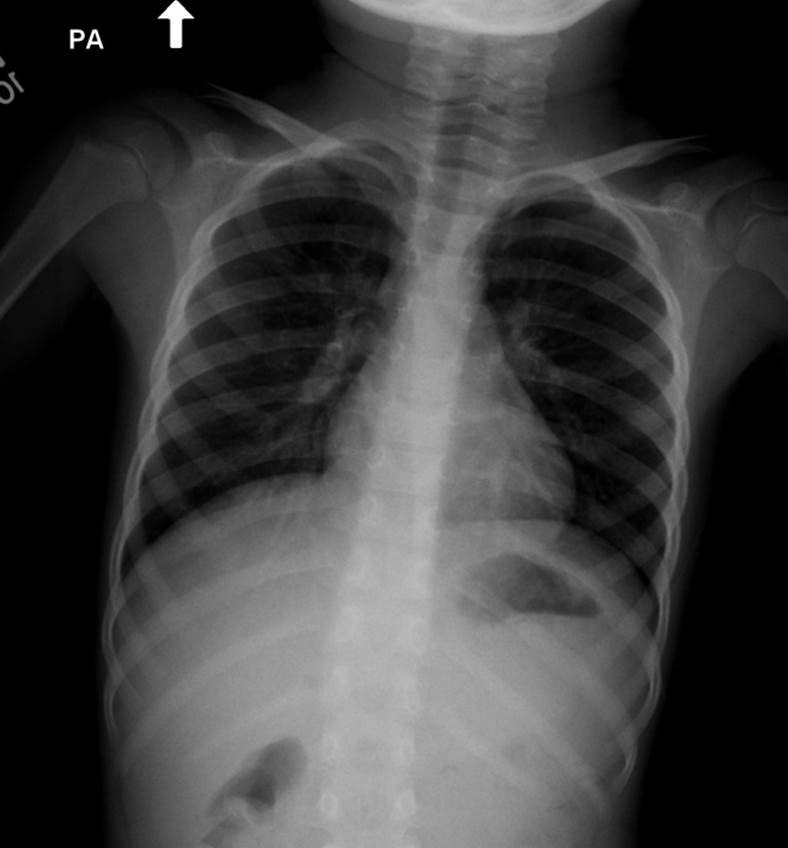

Chest X-ray, Normal, PA